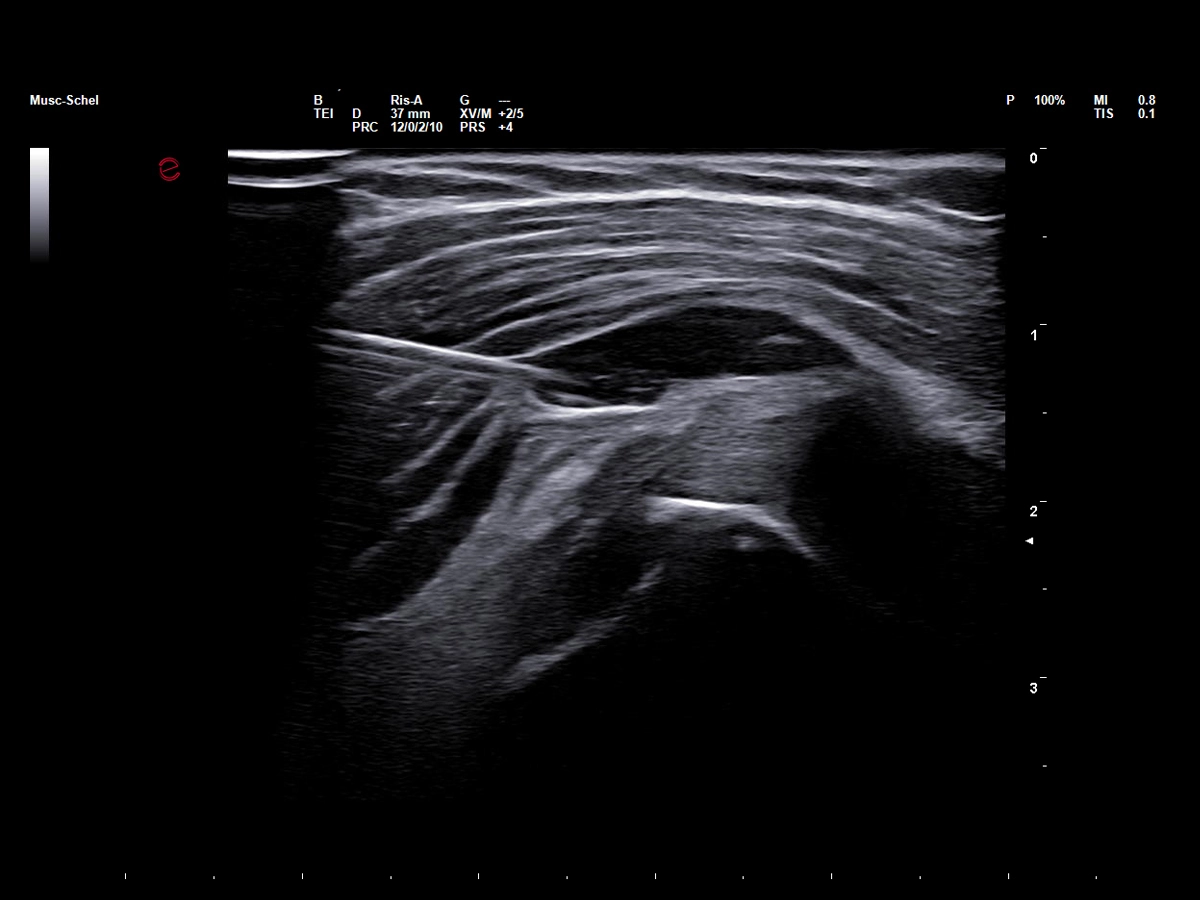

Ultrasound in interventional sports medicine

Precise guidance is pivotal for procedures such as injections (corticosteroids, PRP), aspirations, and dry needling in diagnosing and treating injuries involving muscles, tendons, ligaments, and joints. Ultrasound guidance enhances precision, especially when using Esaote’s Needle Enhancement tool, which improves needle visibility for safer, more accurate procedures. Esaote’s Virtual Navigator (VNav) enables fusion imaging, combining real-time ultrasound with CT or MRI datasets—particularly valuable for joint injections, tendon or muscle biopsies, and other complex cases, as it boosts diagnostic accuracy and procedure planning.